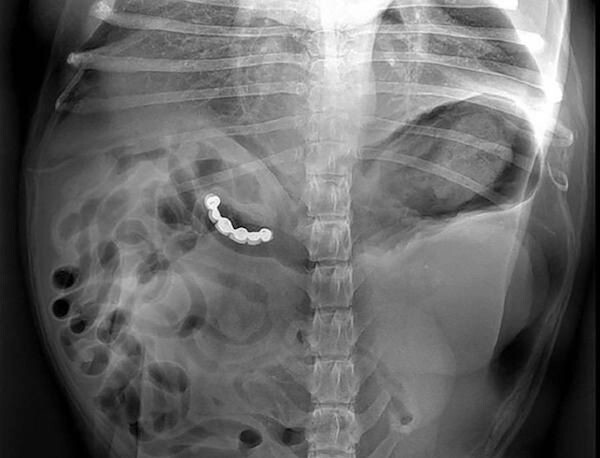

12. Ложка